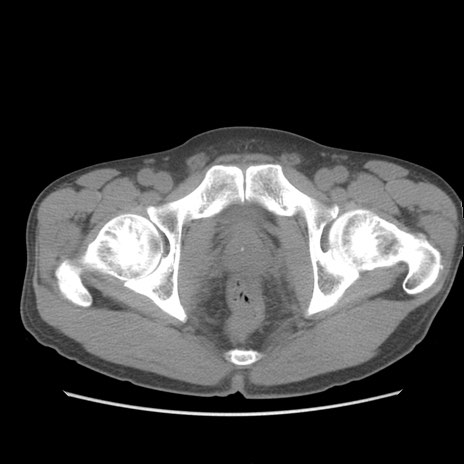

症例56 CT(横断像)

脂肪ウインドウ